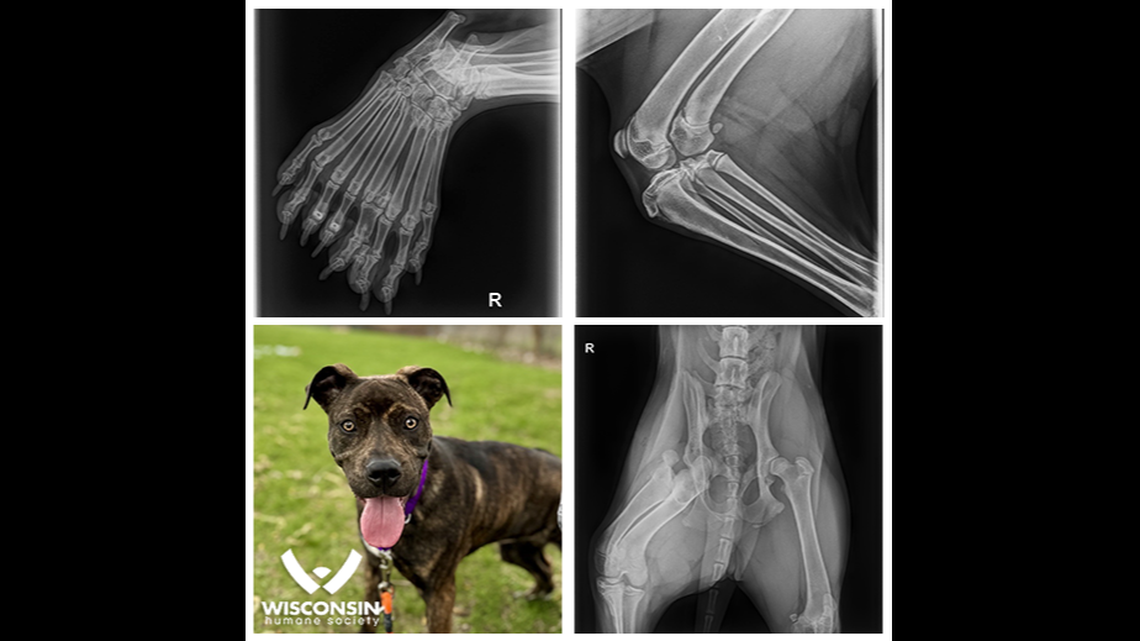

X-rays revealed Bella has a rare condition called dimelia which caused her to grow an extra leg inside her right, hind leg, according to the shelter’s April 25 Facebook post.

Her hind leg has two femurs, two tibias, two fibulas and nine toes, according to the shelter. A typical dog leg has one femur, tibia and fibula and about four to five toes.

She’s the “first ‘five-legged’ dog we’ve seen in our 145 year history,” the shelter said. It’s a congenital anomaly that causes a dog to grow duplicate bones.